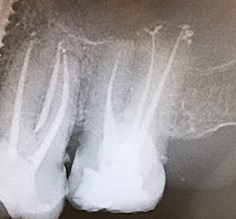

Una corretta terapia canalare con un perfetto sigillo a livello degli apici delle radici è fondamentale. I denti devitalizzati impropriamente possono creare ulteriori problemi che poi andranno a ripercuotersi sulle cure effettuate successivamente come le ricostruzioni e le corone protesiche con conseguente fallimento del piano terapeutico.

Capita spesso di incontrare denti già devitalizzati in maniera impropria che necessitano, seppur asintomatici, di essere ritrattati per evitare che i granulomi infetti visibili radiograficamente si evolvano riassorbendo tutto l’osso sottostante.